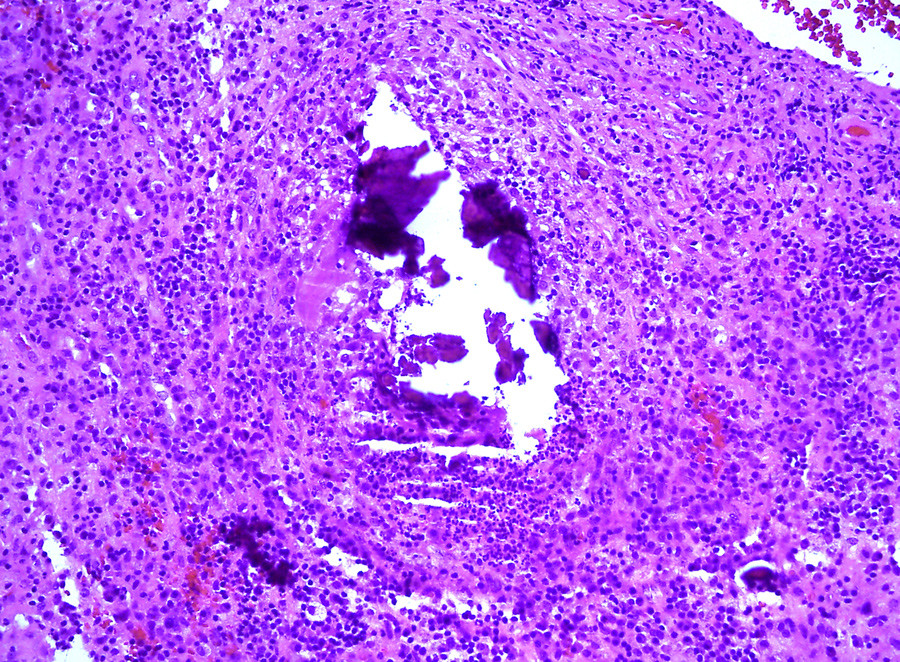

Åtte dager etter første innleggelse ble det i narkose høstet biopsimateriale og dyrkingsprøver fra prevertebralt område ved C1 – C2. Prøvetaking ble gjort via vertikal incisjon gjennom slimhinne og ligamentum longitudinale anterius. Inngrepet ble gjennomført transnasalt under endoskopisk veiledning (fig 2). Frysesnittundersøkelse og senere endelig histologi viste ikke tegn til malignitet, kun inflammatoriske forandringer med innslag av kalk eller beinrester (fig 3). Svar på dyrking fra prevertebralt område, i tre forskjellige prøver, viste penicillinresistente Staphylococcus aureus.

På grunn av forholdene rundt prøvetaking og vurdering av radiologiske, histologiske og mikrobiologiske funn ble histologi og dyrkingssvar vurdert som representative. Antibiotikabehandling ble iverksatt etter svar på frysesnittundersøkelsen, samme dag som biopsi ble tatt.